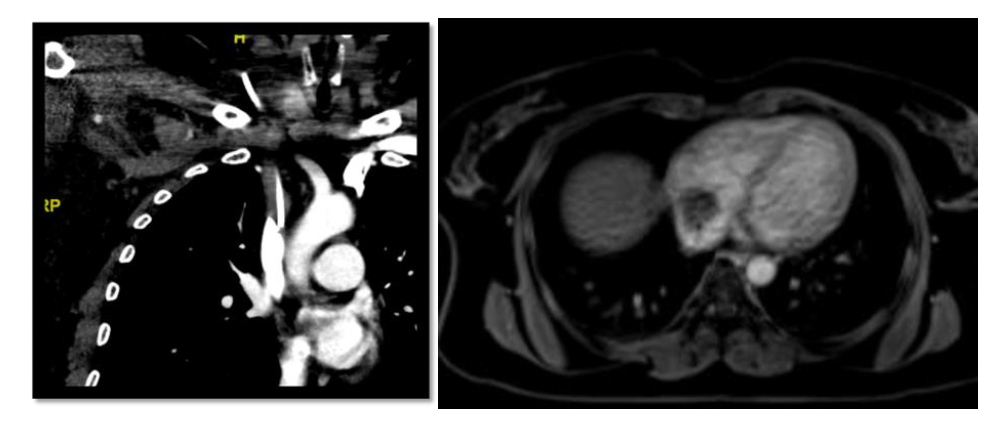

Fifteen patients (1.48%, 0.041/1000 catheter days) developed catheter dysfunctions (11 thrombotic and 4 nonthrombotic). Only 1 out of 11 thrombotic dysfunctions developed early, which occurred after 27 catheter days. The patient developed catheter occlusion, which was proven on a patency check done in the IR suite. Five out of 11 ports were explanted (port removal for fibrin sheath formation shown in Figure 4) and the remaining 6 were successfully treated with thrombolysis with urokinase (Figure 5). The thrombotic complication with fibrin sheath formation occurred as late as 1206 days, which was treated with thrombolysis using urokinase.

There were 3 catheter migrations and 1 port rotation. Catheter migrations (Figure 4) were noticed to migrate into the right IJV, right brachiocephalic vein, and left subclavian vein. All these patients underwent explantation and reinsertion of the ports. One of the patients whose port was migrated to the right IJV was admitted for chemoport removal and reinsertion. However, during the manipulation of the displaced port catheter, she began experiencing severe rigors in the IR suite. She was afebrile and hemodynamically stable; the procedure was abandoned, the port removed, and the patient shifted to the ward immediately. Cultures were drawn and she was started on I.V. cefoperazone-sulbactam, along with teicoplanin. She went into septic shock that evening and I.V. cefoperazone-sulbactam was changed to injected. Meropenem at a 2-g loading dose was followed by 1 g every 8 hours. She was resuscitated with fluids and remained hemodynamically stable afterward. One port rotation in the chest wall was incidentally detected on a follow-up computed tomography (CT) scan of the chest, but the patient had already completed chemotherapy so no treatment was sought.

Twelve patients developed venous thrombosis (1.19%, 0.032/1000 catheter days), out of which 2 were early and 10 were late. Two patients developed right IJV thrombosis (Figure 5) at 23 and 26 catheter days, which was treated with port removal followed by heparin. Regarding late venous thrombotic complications, the latest occurred after 662 days and was treated with heparin. Two patients with IJV thrombosis concurrently developed other complications, one with concurrent port site infection and the other with catheter tip migration. After 130 days, one of the patients presented with signs and symptoms suggestive of SVC obstruction. An emergency CT thorax was done that confirmed the diagnosis and showed extensive thrombosis involving the right IJV, bilateral brachiocephalic veins, and SVC. She was started on anticoagulation with injected dalteparin and an IR consult was sought. We performed thrombolysis, thrombectomy, and plasty. Following the procedure, she was kept under close monitoring in the ICU for 1 day, after which she was moved to the ward. One of the patients developed a right atrial thrombus (Figure 6), and another developed a left atrial thrombus.